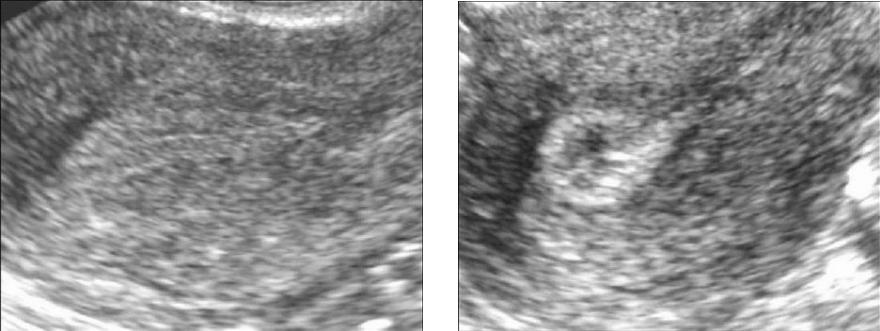

При проведении ультразвукового исследования (УЗИ) можно заметить признаки гиперплазии, которая проявляется в виде небольших участков размером от 2 до 7 мм, распределенных по всей поверхности эндометрия. Эти участки имеют неправильную форму и четкие контуры. В такой ситуации признаки эхогенности остаются стабильными на протяжении всего менструального цикла.

Диагностика

Эгиперэхогенность эндометрия выявляется во время ультразвукового обследования с использованием трансвагинального или трансабдоминального датчика. При этом равномерное увеличение эхогенности по всему эндометрию считается нормальным для определенных фаз менструального цикла. Однако случаи, обсуждаемые в данной статье, обладают другими визуальными признаками. Это проявляется в виде светлых участков с повышенной эхогенностью на фоне более или менее нормального эндометрия.